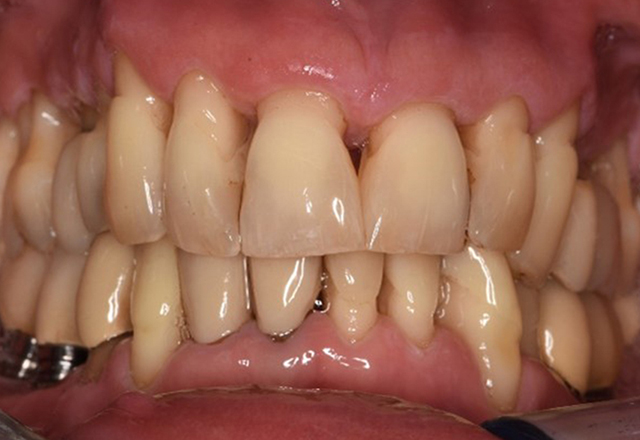

La paziente sana con precedente patologia parodontale

Questa paziente di 68 anni non presenta alcuna patologia precedente né segue alcuna terapia che possano ritenersi rilevanti dal punto di vista odontoiatrico, e il suo stile di vita non comporta alcun rischio particolare. La paziente ha due impianti (3° quadrante, da cinque anni) e una precedente patologia parodontale (parodontite allo stadio IV, grado B) con perdita del dente. Al momento le condizioni parodontali sono stabili, tuttavia la parodontite aumenta in misura significativa le complicazioni biologiche degli impianti e c'è dunque il rischio di perdita dell'impianto (21). Per la seduta di profilassi si possono formulare quattro consigli. di più